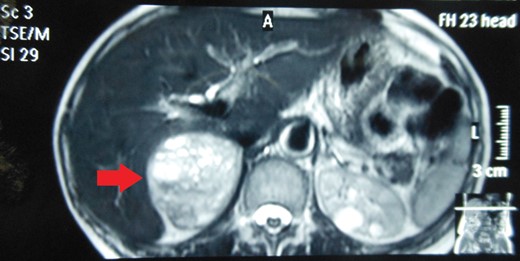

Routine laboratory tests were unremarkable. Ultrasound of the abdomen showed a 5 × 5 cm solid-cystic mass overlying the right kidney. CECT abdomen confirmed the presence of a right suprarenal tumour measuring 6 × 5 × 5 cm with solid-cystic components and fluid levels suggestive of intratumoural haemorrhage. Magnetic resonance imaging (MRI) of abdomen suggested an space occupying lesion in the right adrenal gland with multiple cystic spaces of variable sizes suggestive of pheochromocytoma. Fat planes to the adjacent structures were preserved with no evidence of metastases (Figs 1–4).

MRI abdomen showing a hyperintense right suprarenal mass (TRANSVERSE SECTION).